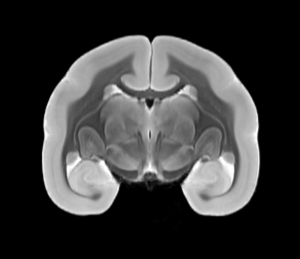

Original T2WI MRI Brain (Coronal View)